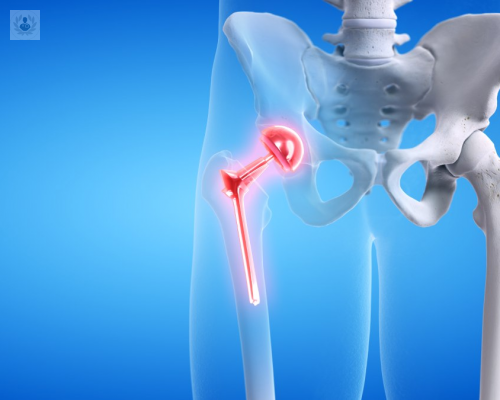

La artrosis de cadera es un padecimiento crónico y para el tratamiento de casos muy avanzados se puede indicar el reemplazo de cadera. Se trata de un procedimiento quirúrgico extremadamente reglado y estandarizado, el cual debe ser realizado por un equipo de especialistas para garantizar los mejores resultados. Conozca los detalles sobre esta intervención